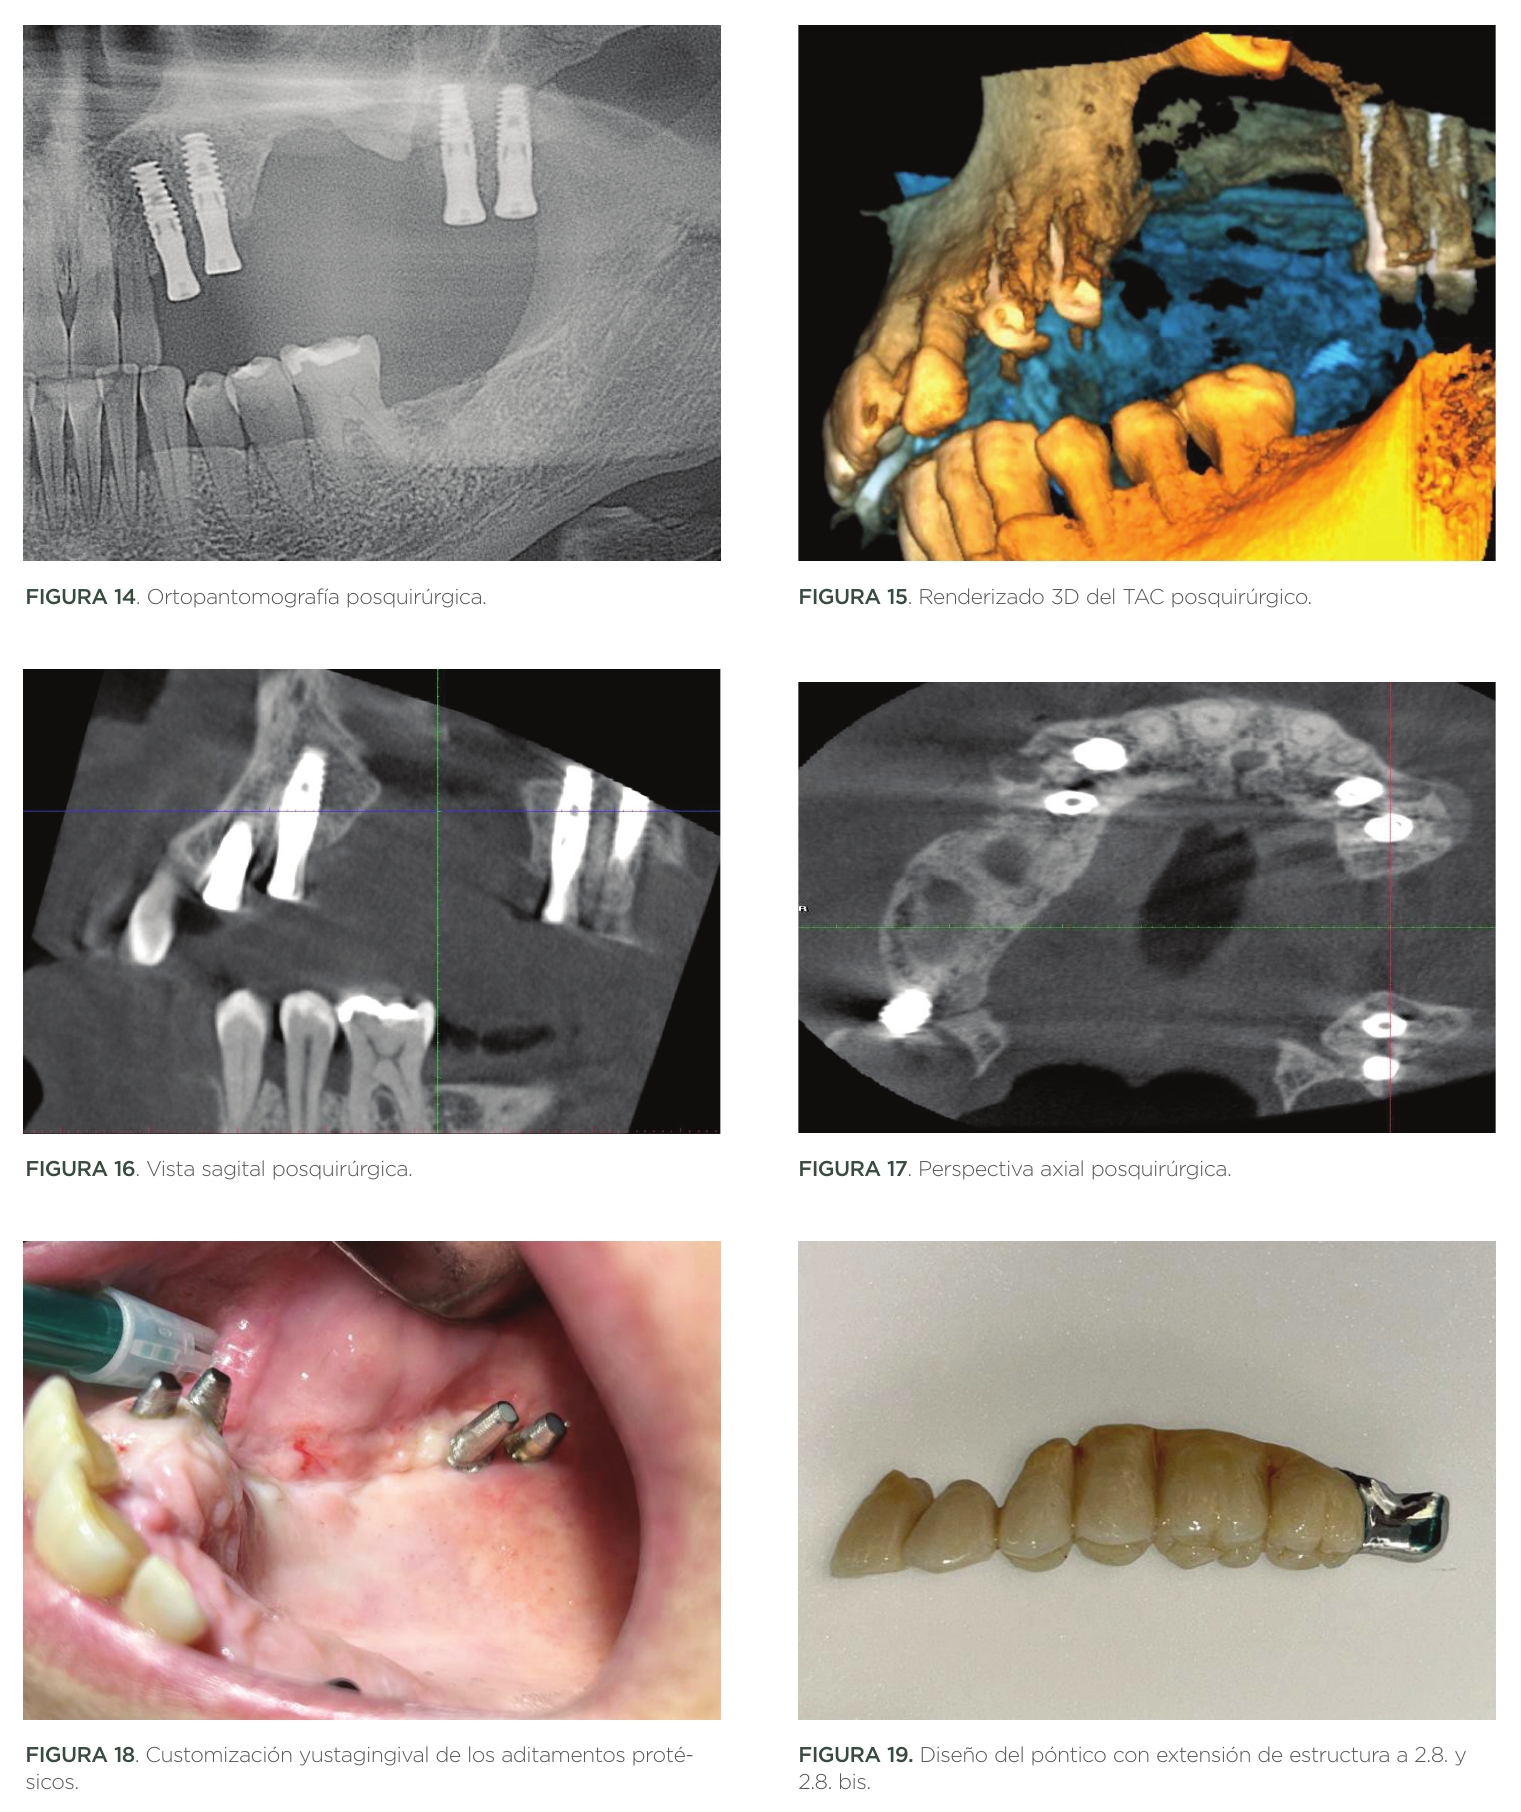

Los implantes posteriores fueron insertados en zona 2.8. y 2.8. bis por motivos de baja disponibilidad ósea. En esta zona, el hueso de densidad D4 obligó a la preparación del lecho mediante site formers para aumentar la densidad ósea periimplantaria (Figuras 14,15,16,17).

Los implantes fueron rehabilitados mediante aditamentos protésicos atornillados para prótesis cementada. Dada la patología periodontal de la paciente, estos pilares protésicos fueron customizados directamente en boca para ajustar la línea de terminación a la altura yuxtagingival.

Para la rehabilitación protésica del caso, se optó por la realización de un póntico de seis piezas de 2.2. a 2.7.

Debido a los vectores de deflexión, y a la longitud del póntico, el material de confección escogido fue la combinación Titanio-Gradia®.

Este póntico disponía la pieza 2.2. en cantilever, y una prolongación de estructura metálica sin recubrimiento estético en zona 2.8. y 2.8. bis (pterigoidea) (Figuras 18,19,20,21).